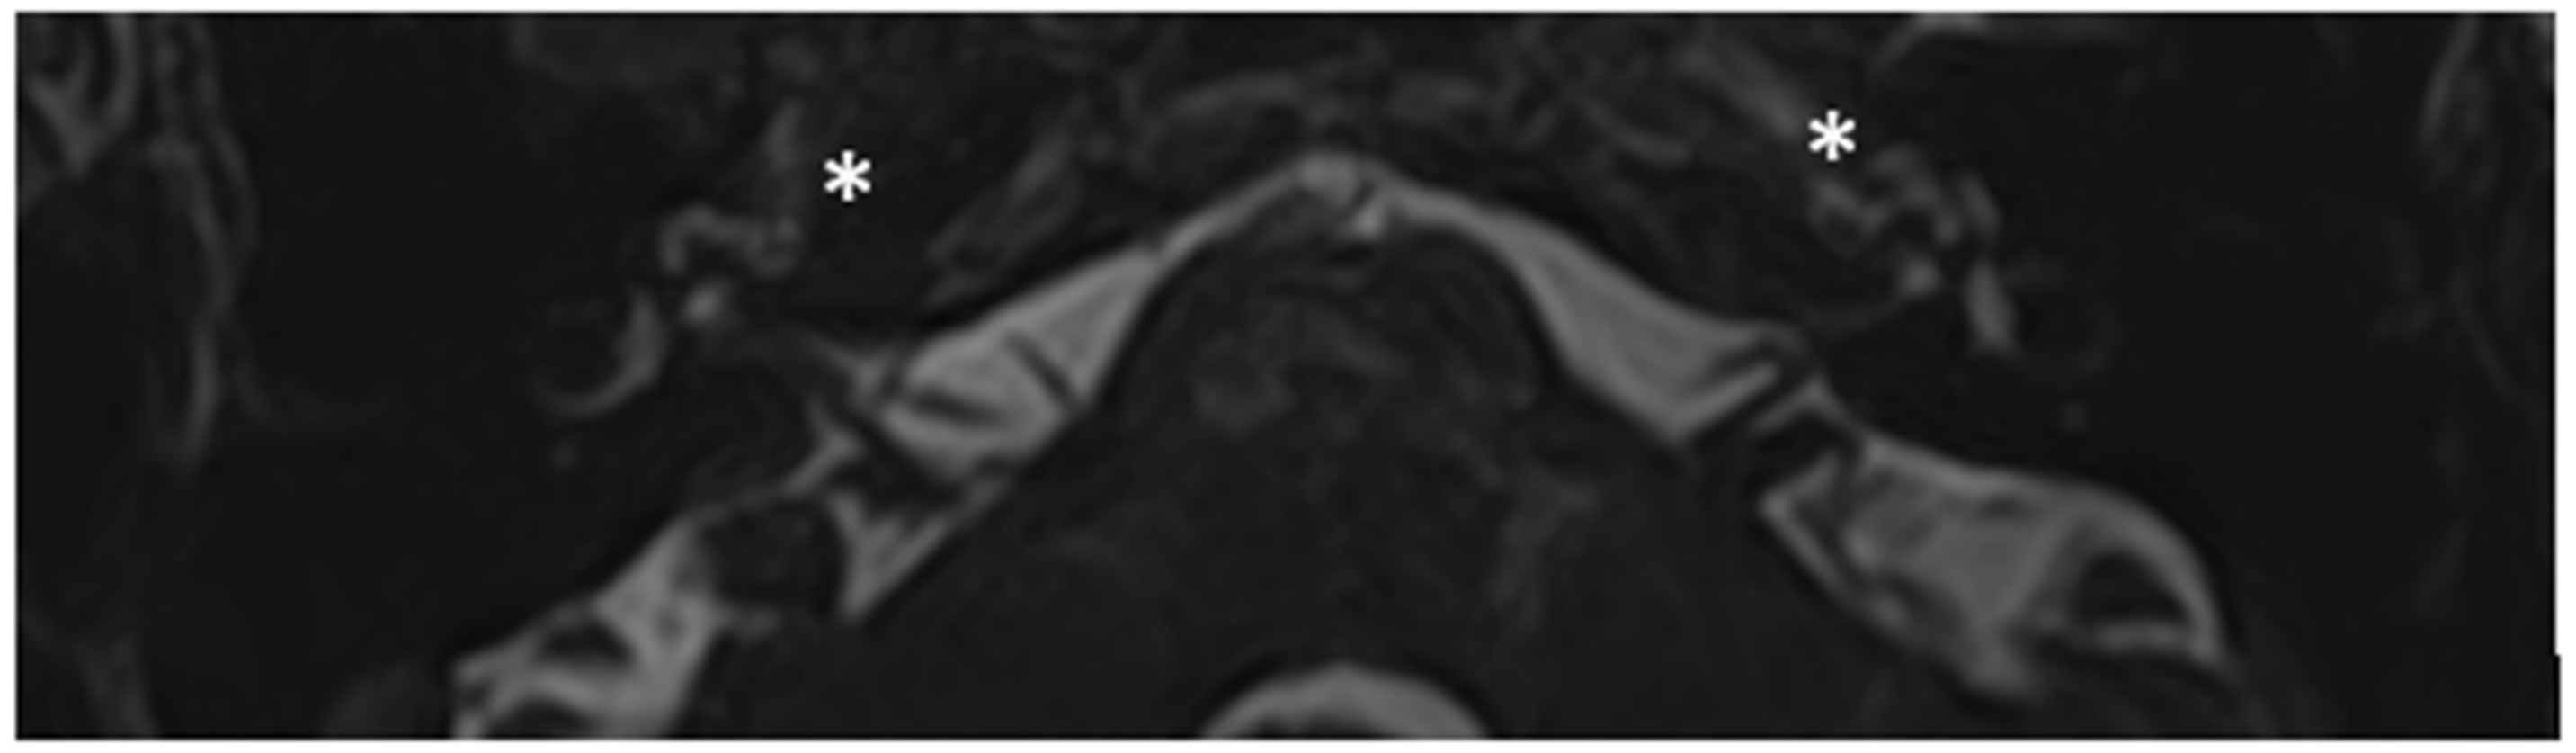

Patient #2, affected by OI-type I (COL1A1 mutation). MHL since diagnosis. Bone threshold was similar in both ears, but PTA was worse in the right ear with a larger ABG. HL progressed, but the difference between the two sides was maintained. The patient was fitted with conventional hearing aids bilaterally. Stapes surgery was not performed because of the radiological aspect (Figure 3 and Figure 4): a large cavity is present bilaterally and diffused communication between the cavity and the cochlea is evident.

Figure 3.

CT images of patient #2 with osteogenesis imperfecta. (A), axial plane; (B), coronal plane. A large pericochlear cavity is visible; arrows indicate its origin from the IAC, asterisks indicate the communication of the cavities with the cochlea.

Figure 4.

MR images of patient #2 with osteogenesis imperfecta. MR cisternography: (A), axial plane; (B), coronal plane. Note the fluid-signal in the newly formed cavities (white asterisk).